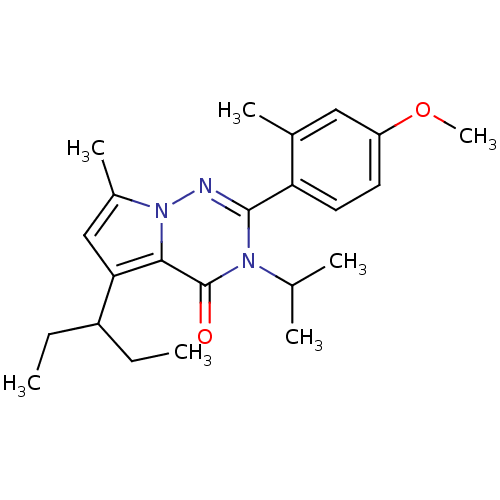

TargetCorticotropin-releasing factor receptor 1(Homo sapiens (Human))

Dupont Pharmaceuticals

Curated by ChEMBL

Dupont Pharmaceuticals

Curated by ChEMBL

Affinity DataEC50: 0.600nMAssay Description:Antagonist activity at human CRF1 receptor expressed in CHO-K1 cells assessed as CRF-stimulated cAMP accumulation by enzyme immunoassayMore data for this Ligand-Target Pair